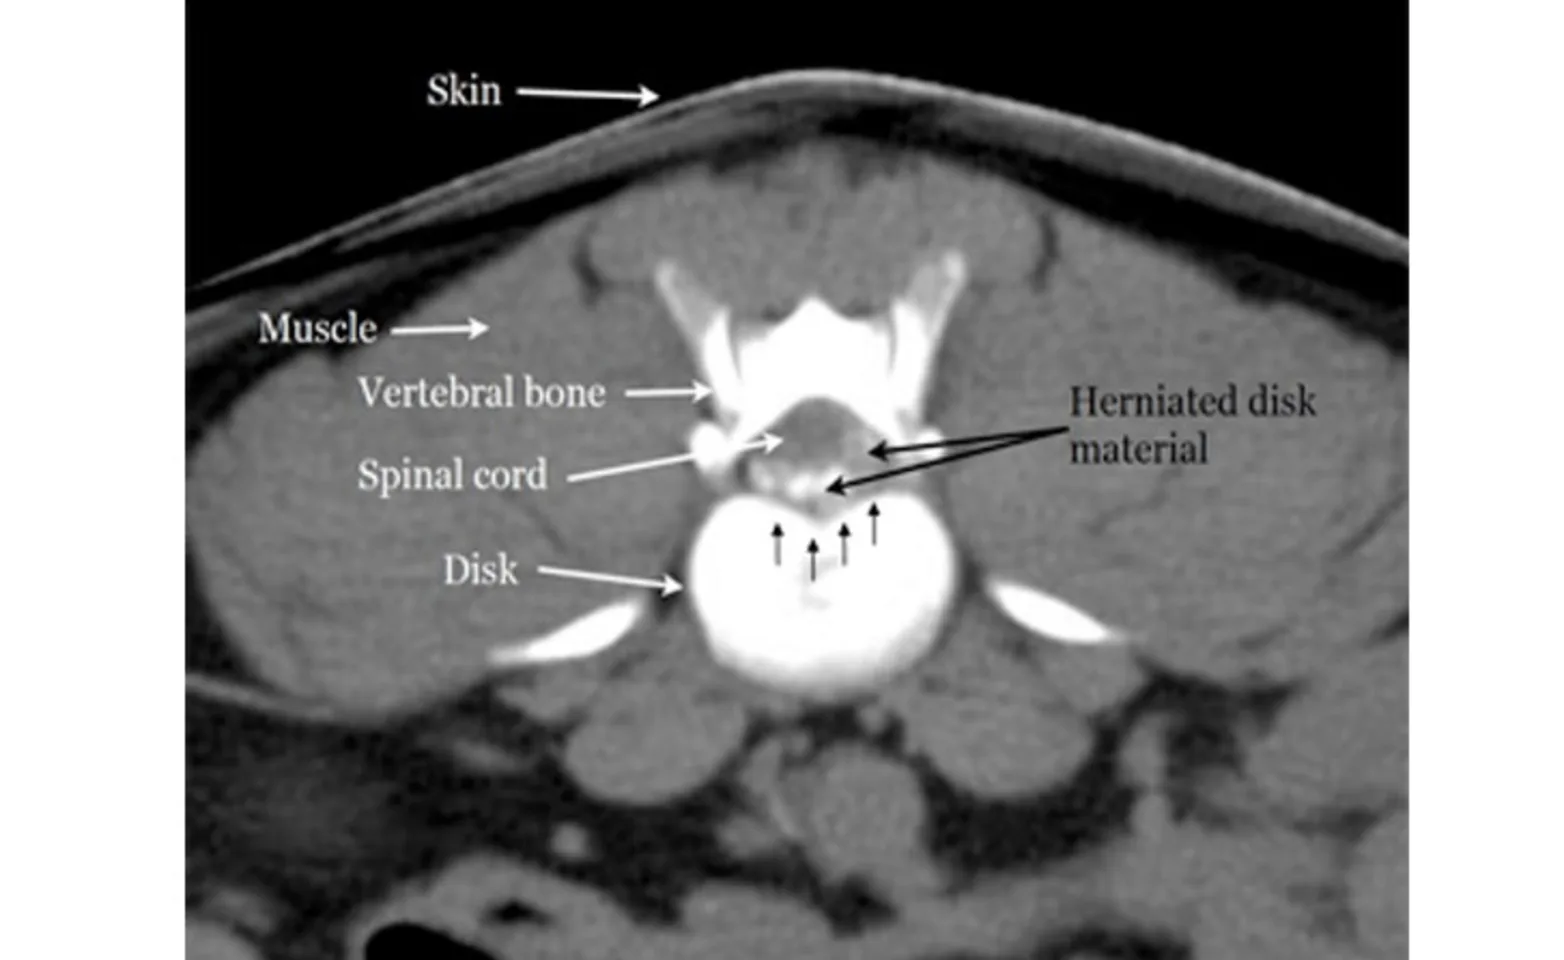

Computed Tomography (CT scan) (Figures 8 and 9) is an excellent imaging technique for IVDD. A CT scan involves the use of x-rays to collect axial images, which are cross-sections, or “bread slices” of the spine. CT is excellent for evaluation of bone detail, and is ideal for visualizing bone tumors, spinal fractures, and diskospondylitis (disk infections). In Type I IVDD, the disc material that is extruded is often mineralized or calcified. This mineralized disc material can be easily seen on a CT scam. In larger dogs, non-chondrodystrophic dogs, or dogs with type II disc disease, the disk may not be significantly mineralized. In these patients, a myelogram in combination with a CT scan may be necessary.

Figure 9. A CT image of the spinal cord and extruded disk causing compression.